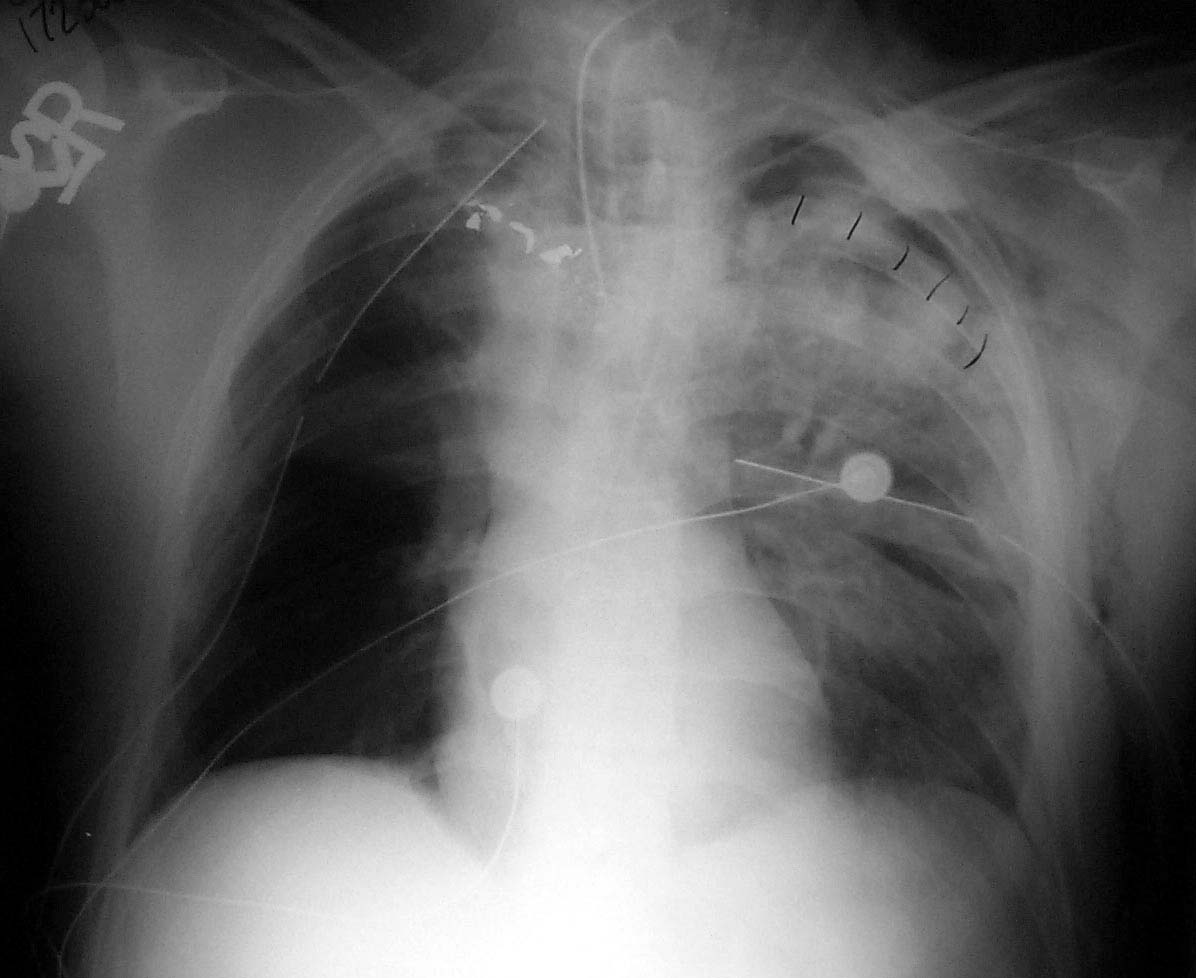

Enclosed are three figures--the CXR of a male with a left to right transmediastinal GSW of upper chest--no hard signs of vascular injury except for about 1000 cc blood out of left chest tube which eventually stopped without surgery. Next is angio #1 showing intimal defect in innominate artery right at the takeoff of the Rt subclavian and carotids. F/U angio one week later--no surgery--documents complete resolution of the intimal injury. There were no symptoms, including the blood from the left chest, attributable to this injury, thus fulfilling the criteria for observation.

Initial Angio